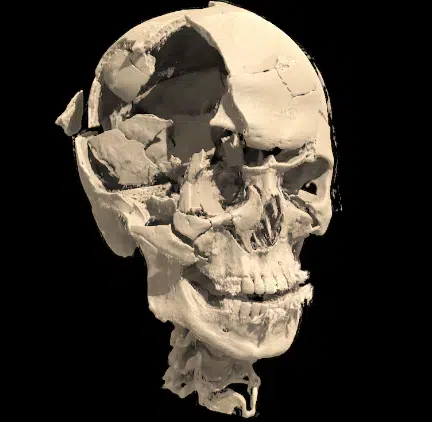

Imagens divulgadas pela Polícia Federal nesta segunda-feira (18) mostram que parte do crânio de Francisco Wanderley Luiz, autor do atentado em frente ao STF (Supremo Tribunal Federal), ficou destruído após o lançamento dos explosivos. Com a tomografia feita no autor, foi identificado que o lado direito da cabeça foi parcialmente destruído, além de rachaduras nas demais áreas.

“Constatou uma fratura extensa, com abertura do crânio no lado direito, e várias fraturas com amputação dos dedos na mão direita. O que é compatível, nos permite inferir, que essas regiões estavam próximas no momento da explosão, ou seja, provavelmente, ele segurou a bomba com a mão direita próximo da própria cabeça”, disse o boletim do médico legista.

Além das imagens da tomografia, a polícia também divulgou fotos do carro e roupas usadas pelo autor.

Foto: Divulgação / PF